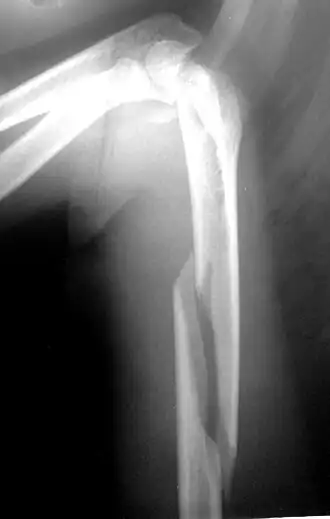

Рентгенограмма при многооскольчатом переломе плечевой кости в нижних отделах. Возможны внесуставные и внутрисуставные переломы плеча в нижних отделах. К внесуставным переломам нижних отделов плеча относятся надмыщелковые переломы, к внутрисуставным переломам — переломы блока, головчатого возвышения плечевой кости и межмыщелковые переломы.

С учётом механизма травмы Надмыщелковые переломы плеча подразделяются на разгибательные и сгибательные. Сгибательные надмыщелковые переломы встречаются чаще, возникают при падении на согнутую руку. Причиной разгибательного перелома становится падение на переразогнутую руку.

Область плеча над локтевым суставом отечна, резко болезненна. Сгибательные переломы сопровождаются визуальным удлинением предплечья, при разгибательных переломах предплечье выглядит укороченным. Надмыщелковые переломы плеча могут сочетаться с вывихом костей предплечья. Диагноз устанавливается после рентгенографии.

При неосложненных переломах область повреждения фиксируют гипсовой лонгетой на 3-4 недели. При большом смещении отломков и невозможности репозиции выполняют операцию.

Переломы мыщелков

- Лечение

При переломах без смещения проводят иммобилизацию гипсовой лангетой. При переломах со смещением выполняют репозицию под местной анестезией. Если фрагменты невозможно сопоставить, проводится хирургическое лечение (фиксация отломков спицами, пластинами или винтами). Физиотерапевтические процедуры при данном виде переломов плеча противопоказаны. Пациентам назначают ЛФК и механотерапию.